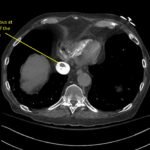

A 78-year-old gentleman presented to the emergency department (ED) for palpitations and dizziness. He had a complicated medical history including atrial fibrillation (AF), recently status post a Watchman procedure, oxygen-dependent chronic obstructive pulmonary disease (COPD), and heart failure with preserved ejection fraction (HFpEF). Point-of-care ultrasound (POCUS) revealed the presence of an intracardiac right atrial thrombus. Computed tomography (CT) angiography confirmed the presence of multiple pulmonary emboli (PE), and extension of the thrombus into the inferior vena cava. Pulmonary emboli are a common complication of thrombus in the right atrium. Management may include anticoagulation, thrombolysis, or thrombectomy. This case highlights that emergency physicians can expedite the diagnosis of intracardiac thrombus by using POCUS. The case presented describes a medically complex patient presenting with symptomatic right intracardiac and inferior vena caval thrombosis complicated by multiple PE. Point-of care ultrasound of the heart and lungs were included in his initial assessment, revealing findings of an intracardiac thrombus, and ruling out multiple other differential diagnoses including pericardial tamponade, pleural effusion, pulmonary edema, and pneumothorax. This finding changed the trajectory of this patient’s evaluation and management, and demonstrates the important role of POCUS in the care of ED patients with undifferentiated cardiopulmonary symptoms.